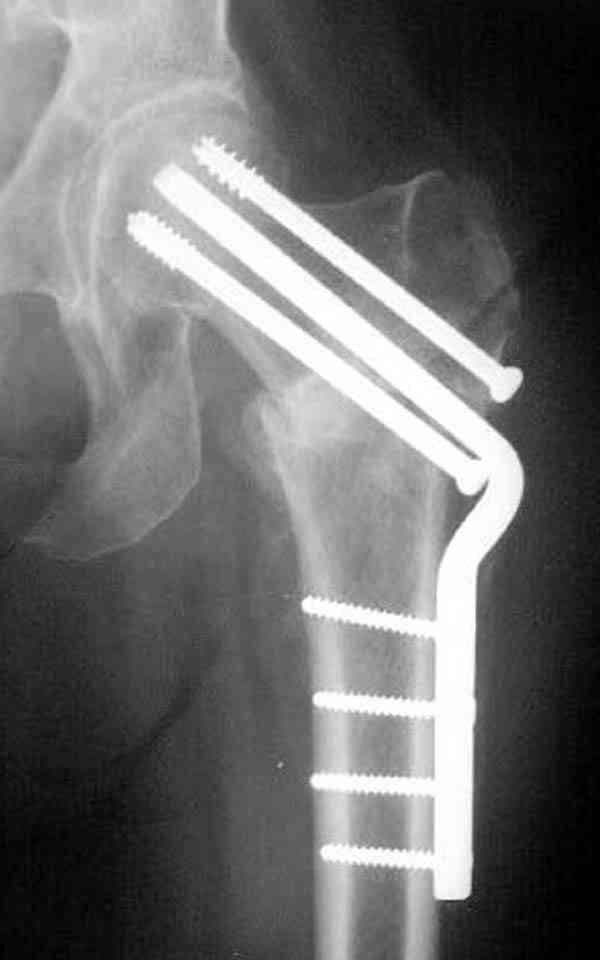

Коллега Челноков прав, здесь еще имеется риск перелома за счет ослабления латерального кортекса. Во время установки канюлированных шурупов за редким исключением спица вводится с одного раза, множественные попытки ослабляют латеральный кортекс, что станет источником перелома в этом месте.

В идеале для профилактики рефрактуры шурупы надо вводить не больше, чем под 130 градусным углом и не ниже уровня малого вертела.

Насчет биомеханических преимуществ одного шурупа  тоже возникает вопрос. Если придерживаться канонов механики, для перелома шейки необходимо 3 паралельных шурупа, расположенных ближе к кортикальному слою шейки.

Здесь случай перелома из-за ослабления латерального кортекса через 3 недели после операции на шейке. Шурупы были установлены под большим углом, слабый латеральный кортекс не выдержал нагрузку.